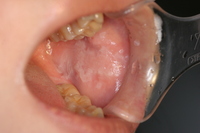

初期の舌癌:白板症のようにも見えますが、組織検査では舌癌でした。